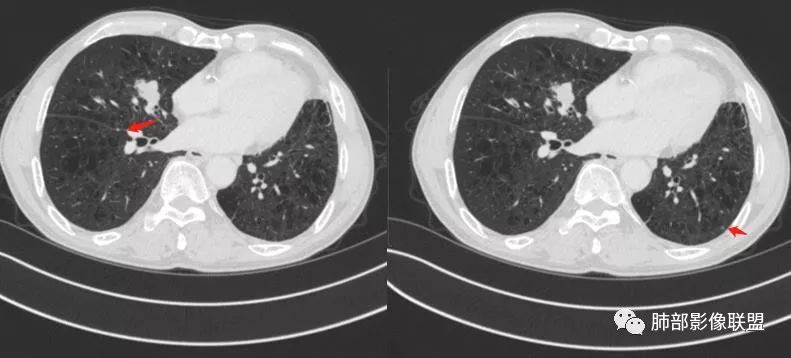

中叶内侧段结节

少许细小结节 医学百科网 | YxBaike.Com

我们的主要目标:中叶内侧段结节

深分叶,部分边缘膨隆,也有部分平直

边缘光滑

部分边缘有短毛刺

我需要看这个是不是近端支气管堵塞,如果近端支气管明确,我就高度怀疑癌 医学百科网 | YxBaike.Com

空泡征 医学百科网 | YxBaike.Com